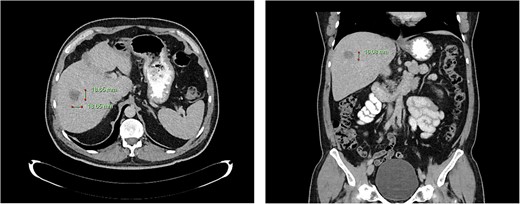

Computed tomography dated 25 September 2012 of the abdomen and pelvis measuring 18.65 mm (anterior–posterior) lesion at liver segment 5/6 in axial (left) and coronal (right) view.

A 44-year-old Mr TM presented in October 2011 with a 2-week history of rectal (PR) bleeding, pencil-like bowel motions and right upper quadrant pain. Colonoscopy revealed a non-obstructing poorly differentiated upper rectum adenocarcinoma, 10 cm from the anal verge. Completion staging computerised tomography (CT) scan demonstrated multiple liver metastases in Segments 2, 4A, 5–8, maximally 94 mm in diameter as shown in Table 1.

He was deemed suitable for palliative chemoradiotherapy and underwent 13 cycles of FOLFOX and 1 cycle of SIRTEX, eventually ceased because of severe peripheral neuropathy. He responded positively to treatment, with more reduction in the size of both his primary rectal cancer and liver metastasis on serial CT scans.

Subsequent surveillance imaging including magnetic resonance imaging and CT scans demonstrated gradual reduction and eventual complete resolution of the liver metastases (refer to Figs 1–4). Furthermore, routine colonoscopy and a positron emission tomography (PET) scan revealed no evidence of locoregional cancer recurrence nor distant metastatic disease present; essentially rendering the patient cured from an initial diagnosis of metastatic rectal cancer. It has been at least a decade since his initial diagnosis and the patient remains in remission.